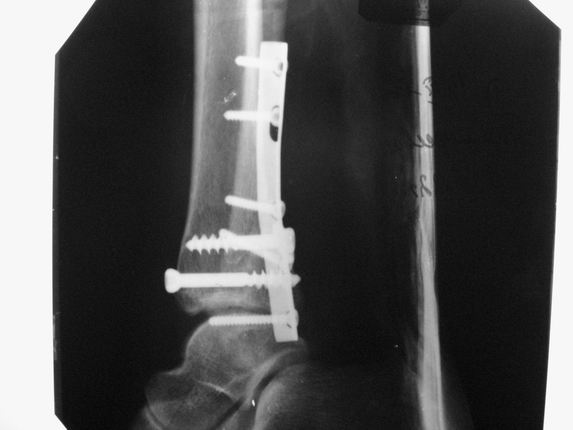

Уважаемые коллеги! Как и обещал, представляю плоды своей работы. Хвалиться особо нечем. Пошли задним

доступом сначала к м/берцовой кости, благодаря смещению линию перелома удалось сразу дифференцировать и по ней узким долотом (без молотка) мобилизовали отломки. Затем выделили задний край, там было проще пройти по линии перелома. Далее пластина по задней поверхности в дистальный отломок, винт проксимальнее пластины и дистрактором с трудом растянули отломки, ощущение было идеальной репозиции м/берцовой кости( доступен осмотр по задней и наружной поверхности), далее винты стандартно. Кстати, положение больной на боку: очень неудобно, но по-другому потом не повернуть на спину, чтобы сделать снимки в стандартных проекциях (ЭОПа нет). Затем дистрактор (два полукольца, спицы), репозиция заднего края, спонгиозный винт с шайбой, слишком проксимально, поэтому + еще один. Доступ к дельтовидной связке: рубец в передней порции, частично иссечен, шов. В общем, длительность операции 3,5 часа, а сказать, что все задуманное получилось, не могу.